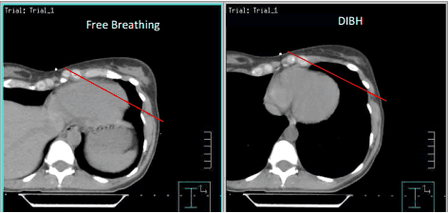

For some patients — especially those with left-sided breast cancer or with tumors in organs in motion (e.g., lung, liver, pancreas) — taking and holding a deep breath moves critical organs farther from the treatment area or fixes a tumor that is typically in motion. With DIBH, your breathing is monitored in real time, and the radiation beam pauses if you fall outside the safe range. Your care team will create and compare treatment plans to determine whether DIBH is right for you.